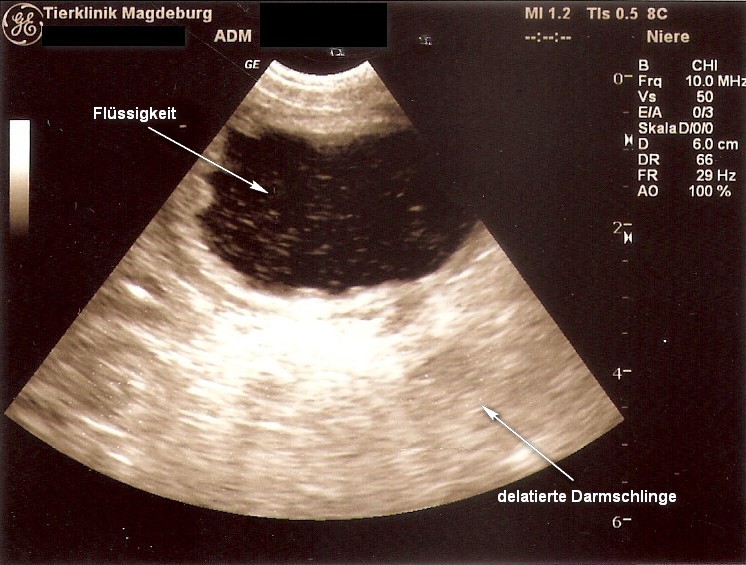

Da der Verdacht nahe lag, dass sich dort noch etwas versteckte, führte

Frau Doktor Leppelt eine Sono und einen weiteren Tastbefund durch - ja

da war doch noch etwas.

Eine

von diesen beiden Kong-Kullern hatte sich schon in einer Darmschlinge

versteckt und die Öffnung in ihr sorgte für den noch minimalen Kot- und

Harnabsatz.

Hier wurde der Übeltäter - Kullerkong - nach einem weiteren eingehenden Tastbefund dingfest gemacht.